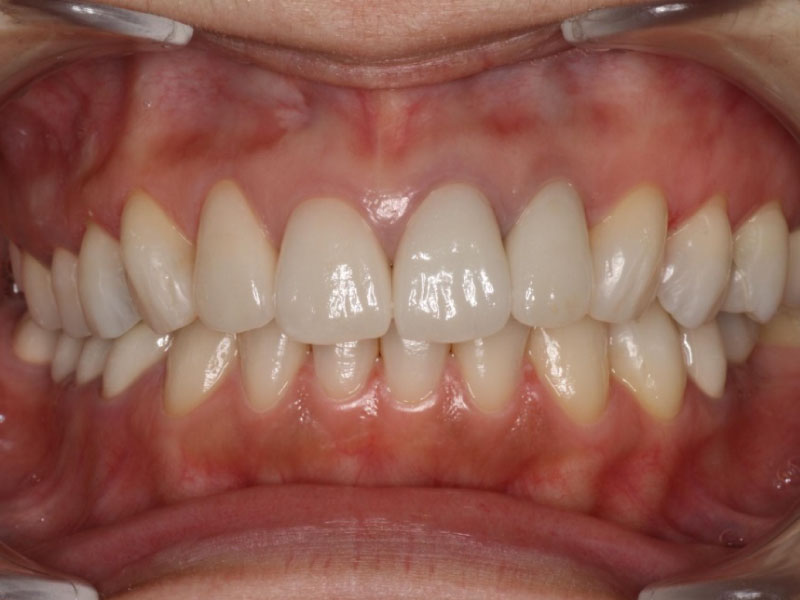

after